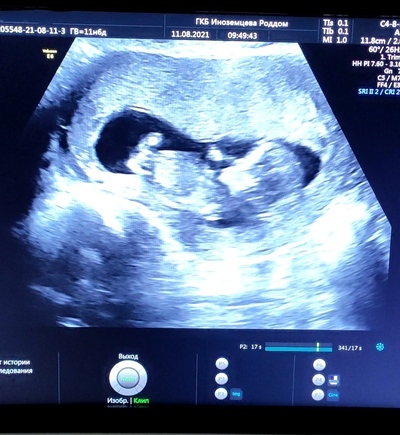

Далее, дней через пять-шесть, каждый из нас был вполне себе успешной бластоцистой, имплантанция которой в стенку матки привела к беременности и собственно к рождению. На фото ниже пример хорошенькой вылупляющейся бластоцисты.